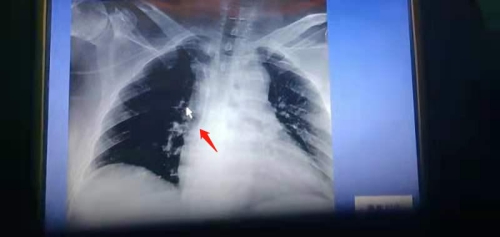

接受手臂输液港手术的是1位63岁的女性乳腺癌患者,手术中,朱晓亮、章新星医生首先对患者预埋血管进行评估,选择穿刺点,并在超声引导下迅速完成置管,继而制作囊袋、埋入港体、缝合切口。手术顺利,术后患者无不适主诉,切口处无渗血、渗液,血管通路输液通畅。

与常用的胸壁输液港相比,手臂式输液港可以有效避免因穿刺而引发的血、气胸,有效规避夹闭综合征的发生;皮下隧道短,减轻患者的疼痛及不适感;不影响患者胸部放疗、胸片摄片;港体小、切口小,更美观,位置更隐蔽,方便患者使用汽车安全带以及女性患者佩戴胸衣,大大提高患者的生活质量。该项新技术的开展,既为患者建立了一条安全、有效、美观的中心静脉输液通路,也为静脉治疗技术手段提供了新的选择。